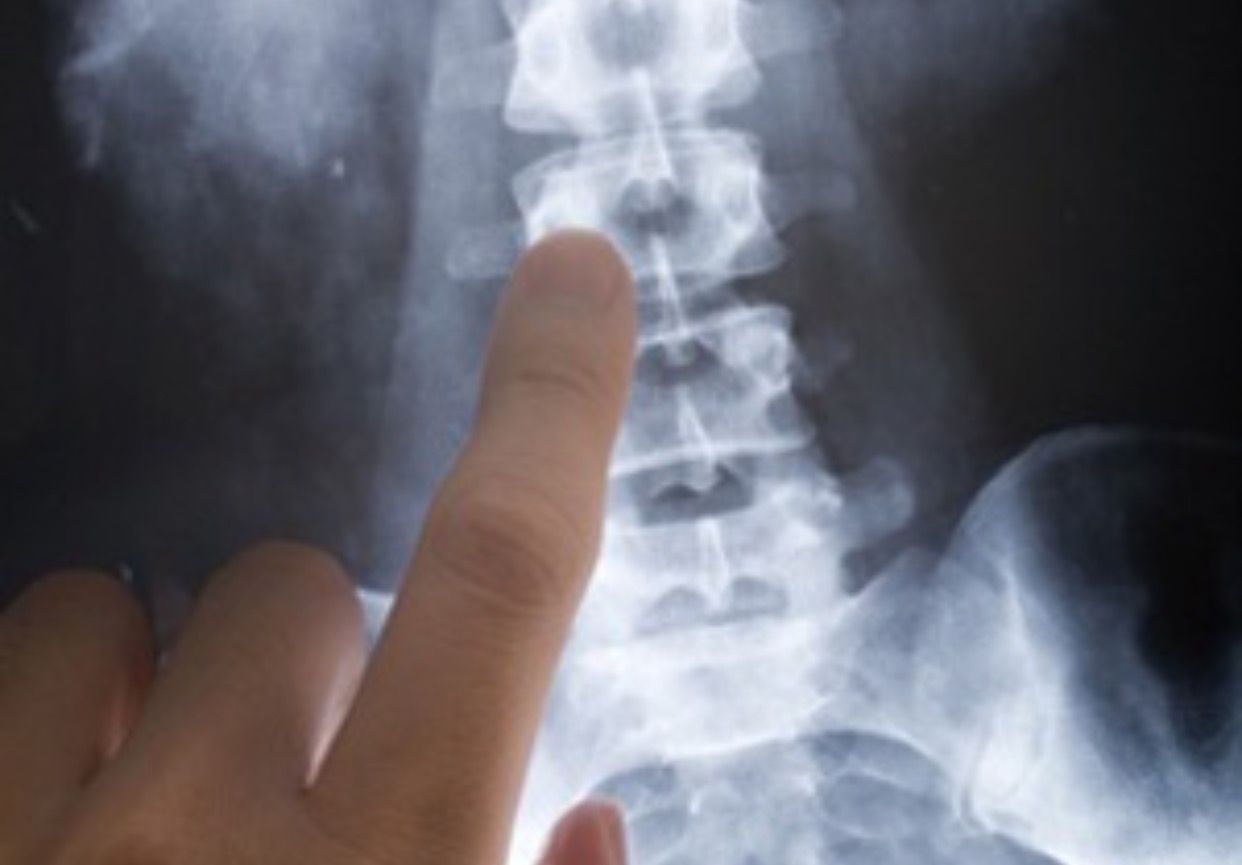

Le procedure che utilizzo, dall'ozonoterapia ai trattamenti con monociti autologhi, dall'acido ialuronico di alta fascia all'idrogel fino alle procedure TC-guidate, non bruciano nessun ponte terapeutico futuro ma lo garantiscono.

• Chirurgia vertebrale

• Ossigeno-ozono terapia